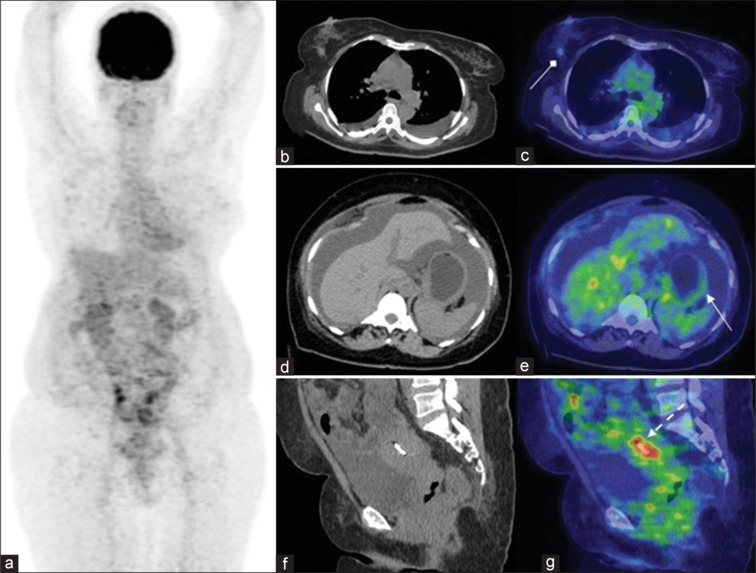

Invasive lobular carcinoma (ILC) of the breast is distinct among breast cancer subtypes due to its unique metastatic patterns, including the involvement of the liver, genital tract, and gastrointestinal tract. As ILC often exhibits low-grade fluorodeoxyglucose (FDG) avidity, the role of fluorine-18 FDG (F-18 FDG) positron emission tomography/computed tomography (PET/CT) in evaluating this subtype remains under re-explored. This case report highlights a rare presentation of ILC of the right breast with concurrent gastric and uterine metastases detected on F-18 FDG PET/CT, emphasizing its diagnostic utility.